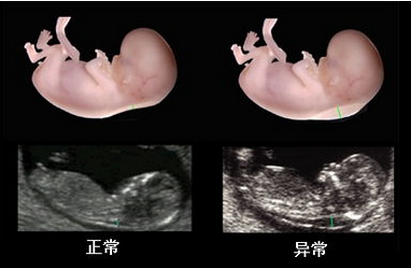

贵阳和谐阳光产科拥有经验丰富的超声科医师,擅长胎儿生长发育评估和胎儿畸形的诊断及胎盘病变的超声诊断。与产科医生无缝接力,对系统彩超的检测筛查准确率高,避免了因医院误诊、经验不足等原因导致孕妇流产、胎儿缺陷等问题。